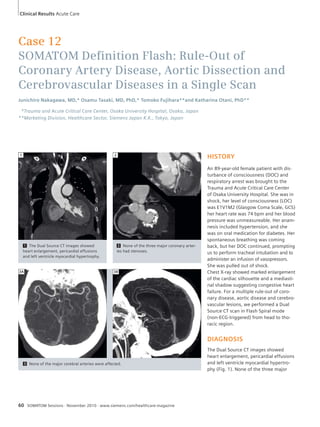

Linköping University Hospital, Linköping, Sweden

1

40 SOMATOM Sessions · November 2010 · www.siemens.com/healthcare-magazine

1 Fused volume-rendered

view showed

variant vascular anat-omy

consisting of

the common hepatic

artery (arrow).

Clinical Results Cardio-Vascular

DIAGNOSIS